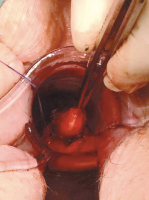

Abbildung 1: Endoskopischer und endosonographischer Aspekt des SMT 2005

Endoskopie

Endosonographie

Onkologie

SMT

submukosaler Tumor